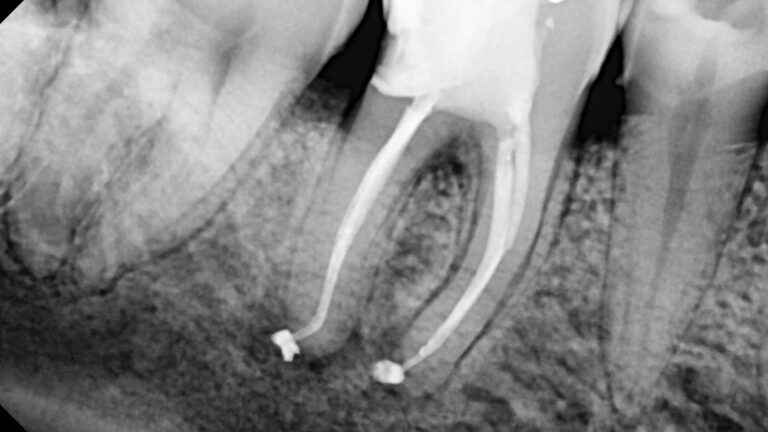

Retratamiento de un primer molar superior con 5 conductos con RetreatAll Conocer fielmente la anatomía interna de los…